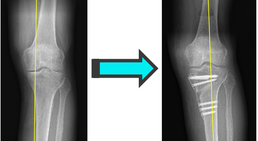

Mein fachärztlicher Schwerpunkt liegt in der Behandlung des Kniegelenks. Durch die internationale Ausbildung an einer Knieklinik, aktive Mitgliedschaft in zahlreichen wissenschaftlichen Fachgesellschaften sowie langjährige Erfahrung führe ich auch komplexe Knieoperationen (u.a. Meniskustransplantation) und Kombinationseingriffe in höchster Fallzahl in Wien durch.